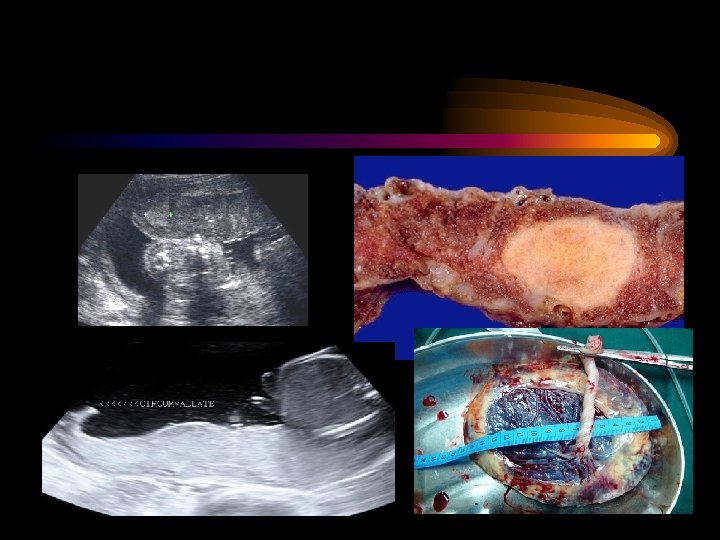

Placental Causes

IUGR: Etiology Fetal / Placental Chromosomal / Genetic Twins Congenital malformation Infectious disease CMV Toxoplasmosis illness Rubella Placental pathology Previa Abruption Mosaiacism Infarction Maternal History of IUGR Hypertension Diabetes MSAFP increase APS Chronic Weight < 90% IBW Hemoglobinopathy Substance abuse Anemia/Hypoxia